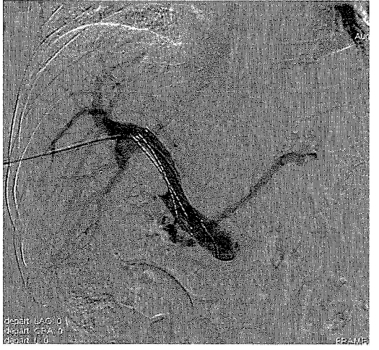

1.12.2第二节 经动脉化疗栓塞术在原发性肝癌中的应用

1.12.2.1一、TACE在肝癌临床治疗中的地位及原理

1.12.2.2二、TACE治疗的解剖学基础

1.12.2.3三、TACE治疗中栓塞剂的选择及作用

1.12.2.4四、TACE治疗的病例选择

1.12.2.5五、TACE操作中的注意事项

1.12.2.6六、TACE的围手术期处理